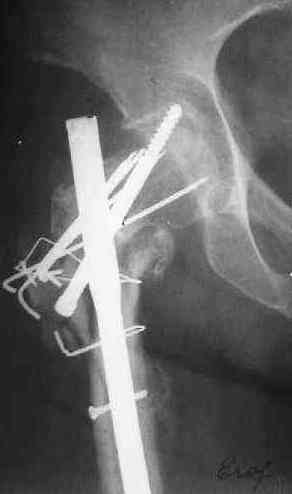

Зажило все без инфекции, свищей не было. Сейчас - есть гиперемия по наружной поврехности бежра. Лейкоцитоз 6,2, но СОЭ - 48 м/ч. Ко всему прочему это наша коллега, работала анестезиологом. Что-то, может быть, сделать дополнительно для обследования?

Other images present the current situation.

Wound healed uneventfully. Now there is local hyperemia at the lateral side of the proximal femur. WBC - 6.2, ESR - 48 m/h.

And the patient is retired anesthesiologist.Maybe some tests should be added?